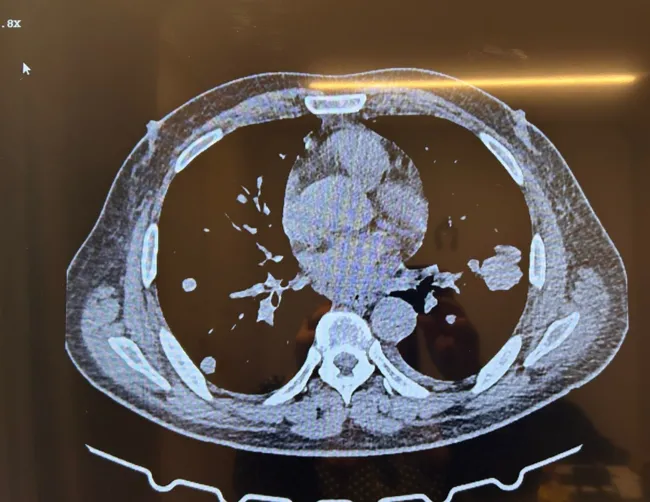

Bir yandan internette araştırmalarını sürdüren ailenin yolu Medikal Onkoloji Uzmanı Prof. Dr. Mutlu Demiray ile kesişti. Mart 2023'te İstanbul'a gelen Bilal Kızak, Mutlu Demiray tarafından muayene edildi. Kişiye özel kanser çalışmaları ile tanınan Prof. Dr. Mutlu Demiray, hastasının genetik haritasını çıkardı, ardından akıllı ilaç tedavisine başladı. İlaçlar yalnızca 2 ay sonra etkisini gösterdi ve tüm tümör kayboldu. Ölümden yaşama yeniden umut dolan Bilal Kızak adeta ikinci hayatını kazandı. Eşi Gülcan, oğlu Birand ve doktoru Mutlu Demiray ile birlikte hastanede mutluluk pozu veren Bilal Kızak, hislerini SABAH'la paylaştı. Kızak, "Akıllı ilaçları kullanıncaya kadar yemeden içmeden kesilmiştim. 20-25 gün içinde yeniden yemeye başladım. İlaçları kullanmayı sürdüreceğim. 3 ayda bir kontrole geleceğim. Artık umut doluyum, korkmuyorum. Yeniden doğmuş gibiyim. Allahıma şükürler olsun" dedi.

Kanserde artık tamamen kişiye özel ve moleküler onkoloji çağına girildiğinin altını çizen Prof. Dr. Mutlu Demiray, Bilal Kızak'ın tedavi süreciyle ilgili şunları aktardı: "Hastalığın hangi organdan kaynaklandığının artık çok bir önemi yok. Sarkom mu veya bir akciğer kanseri mi olduğunun bir önemi yok. Kişiye özel kanser tedavi merkezi olarak öncelikle her hastamızın tümör biyolojisini öğrenmek ve bu öğrendiğimiz biyolojiye göre tedavi dizayn etmek istiyoruz. 'Her hasta özeldir ve her hastanın da kanseri özeldir' prensibinden hareketle hastanın genetik haritalamasını yaptırıyoruz. Bilal Bey, kemoterapi altında tümörü büyümüş bir şekilde ve oldukça da sıkıntılı bir durumda kliniğimize başvurdu. Öncelikle hastamızı anlattık ve biyopsi alarak tümör dokusundan tümörün biyolojisini öğrenmek istedik. Gördük ki hastamızda müdahale edilebilir bir gen var."

"Her genetik mutasyon müdahale edilebilir değil. İşte bu geni bulduktan sonra hastamıza iki tane akıllı ilaç verdik ve iki ay içinde tüm tümör kaybolmuştu. Şu anda hastamız halen tümörsüz bir vaziyette hayatını sürdürmektedir. Ayrıca kanda farklı tekniklerle de kontrol ettiğimizde hastamızın herhangi bir tümörünün olmadığını saptadık. Tabii bu genetik mutasyonu biz saptadık ve ona göre bir tedavi verdik. Müdahale edilebilir bir gen varsa onun akıllı ilaçlarını kullandığınızda gerçekten bu iş sihir gibidir. Bir anda tümörün kaybolduğunu görürsünüz onun için biz her hastanın genetik tümörünün genetik haritalamasını çıkartıp onun üzerinden tedavi dizayn eden bir ekibiz. Tabii ki bu iş bu çok kolay bir iş değil. Biz 4 doktor ve 6 klinik kanser genetikçisi hep birlikte çalışarak bu sonuçlara ulaşabiliyoruz